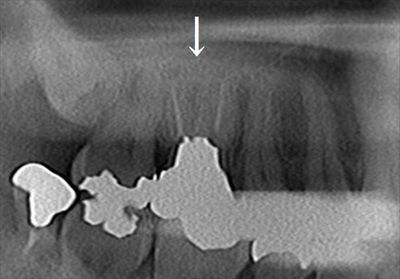

右上第一大臼歯のメタルクラウンとメタルコアを除去しました。2019.09.28.

右上第一大臼歯のメタルクラウンとメタルコアを除去します。

画像下側の口蓋根は内部が浸出液で湿っている状態でした。

根尖(歯根の先端)からの浸出液であり、根管充填が不十分であることを示しています。